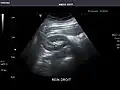

Right kidney -

Kidneys: Right and left kidneys measure 11.5 cm and 12 cm in length respectively. No hydronephrosis. Small left lower pole kidney cyst.